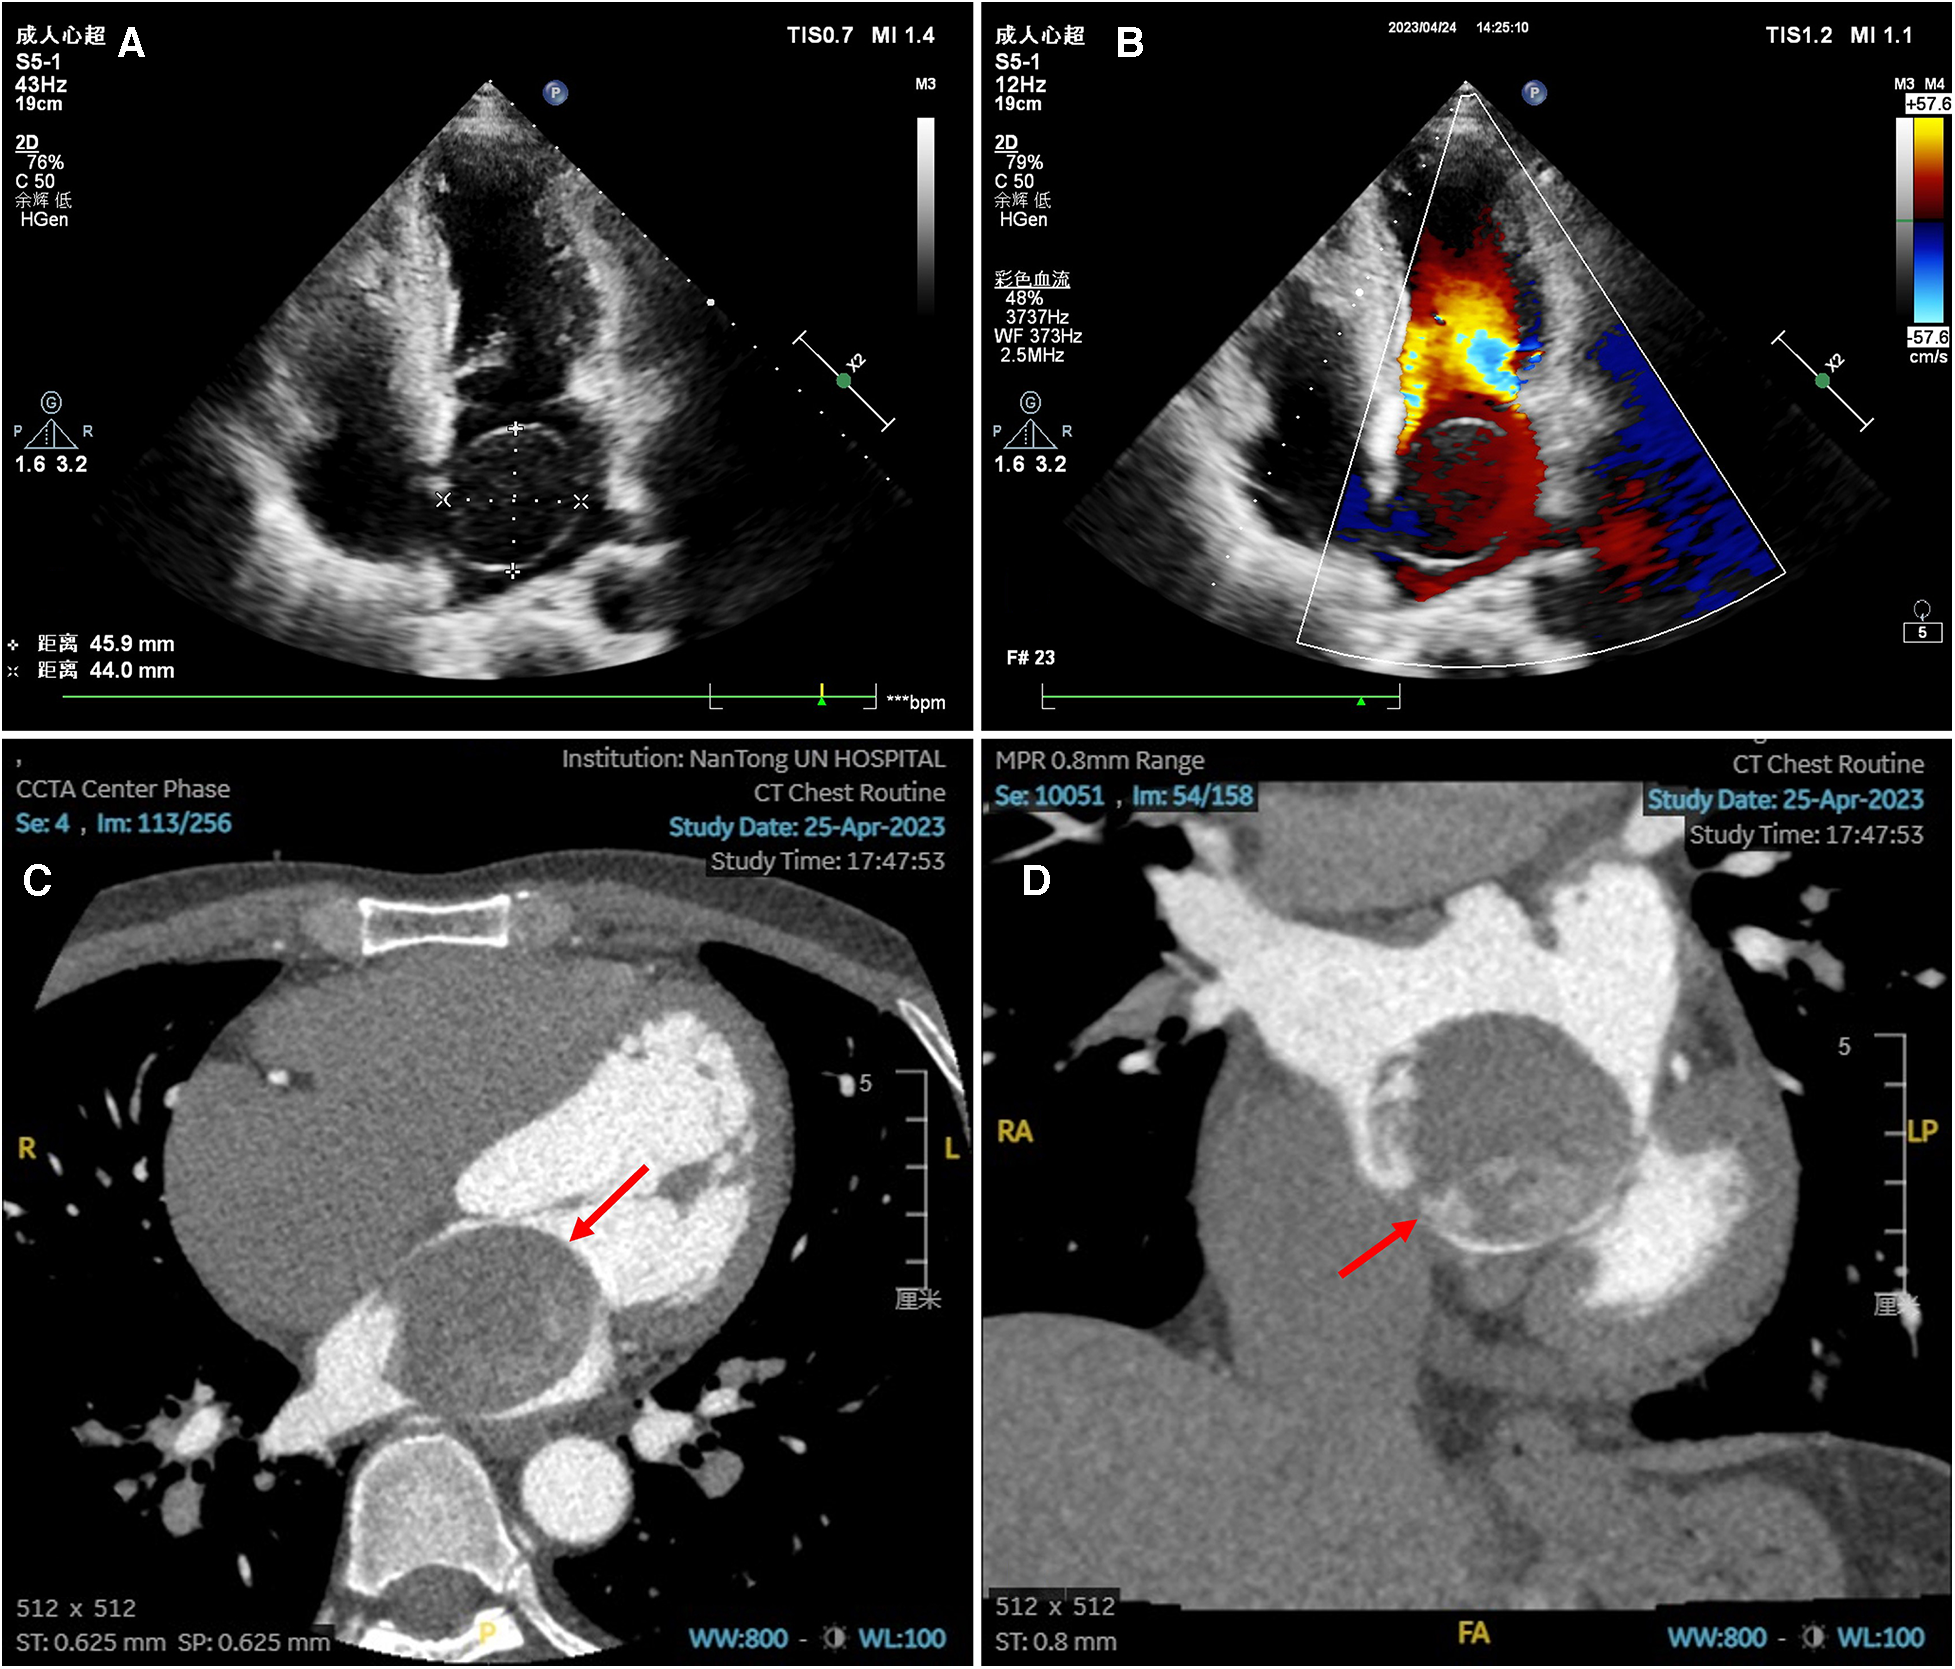

A 43-year-old male patient presented with intermittent dyspnea during sleep for 20 days and underwent TTE at a local hospital, which revealed a left atrial myxoma. He was referred to our hospital for surgical evaluation and was further directed to the cardiothoracic surgery department. The patient denied any history of hypertension, diabetes mellitus, and tobacco use. Upon physical examination, a moderate diastolic murmur was auscultated at the cardiac apex area. Electrocardiography showed a sinus rhythm with a heart rate of 63 beats per minute. All initial laboratory tests were within normal limits, except for a mild elevation in B-type natriuretic peptide (108 pg/L). Additionally, hemoglobin was 143 g/L, albumin was 38.5 g/L, aspartate aminotransferase was 13 U/L, alanine aminotransferase was 12 U/L, erythrocyte sedimentation rate was 2 mm/hour, and Troponin was 0.011 μg/L. TTE demonstrated an almost echoless mass measuring 4.6 × 4.4 cm with well-defined margins in the left atrium, which was attached to the atrial septum with a narrow base (Figures 1A,B). TEE showed a large cystic mass in the left atrium that protruding into the mitral valve during diastole, causing mild mitral stenosis (Supplementary Video S1). A cardiac CT scan displayed a giant tumor located in the left atrium with heterogeneous density following enhancement, suggesting the possibility of a myxoma (Figures 1C,D).

Figure 1

Preoperative echocardiography and enhanced cardiac CT scan images. (A–B) Transthoracic echocardiography showed an echoless tumor measuring 4.6 × 4.4 cm in the left atrium, with clear boundary, a small base attached to the atrial septum, and no blood signal in the tumor. (C–D) Enhanced cardiac CT scan in transverse plane (C) and coronal plane (D) showed a giant tumor in the left atrium with heterogeneous density after enhancement.